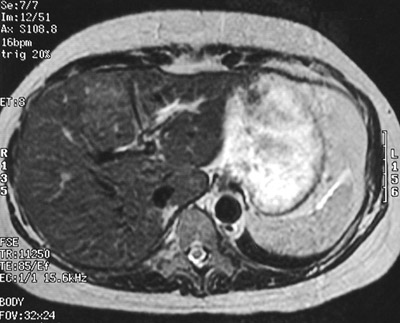

| The abdominal MRI scans in axial view above (T1 weighted) and below (T2 weighted) reveal an area of abnormal signal in the medial aspect of the right lobe of liver with a central bright scar. This is focal nodular hyperplasia (FNH), a slow-growing, hamartomatous process that is uncommon. It occurs more often in women than in men. |